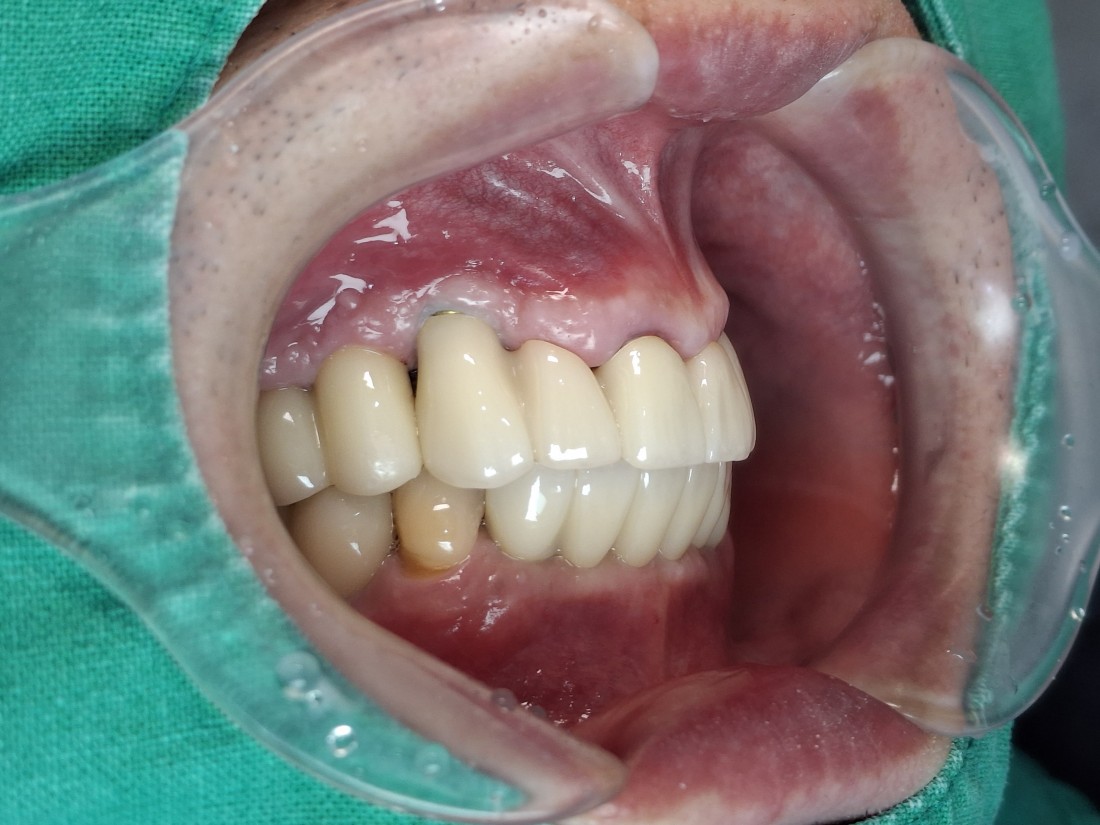

수완동 임플란트 치과는

자체 치아기공소를 운영하고 있습니다.

대표원장인 제가 직접

치아기공소의 보철물 퀄리티를

관리하고 있기 때문에,

무엇보다도

< 예쁘게, 잘 씹어지는 >

수완동 임플란트를 약속드릴 수 있습니다.

잘 관리하면 반영구적으로 사용할 수 있는

임플란트이기 때문에

특히 자연치아보다 더 자연스러운

아름다운 임플란트를 완성하는

수완동 임플란트 치과입니다.